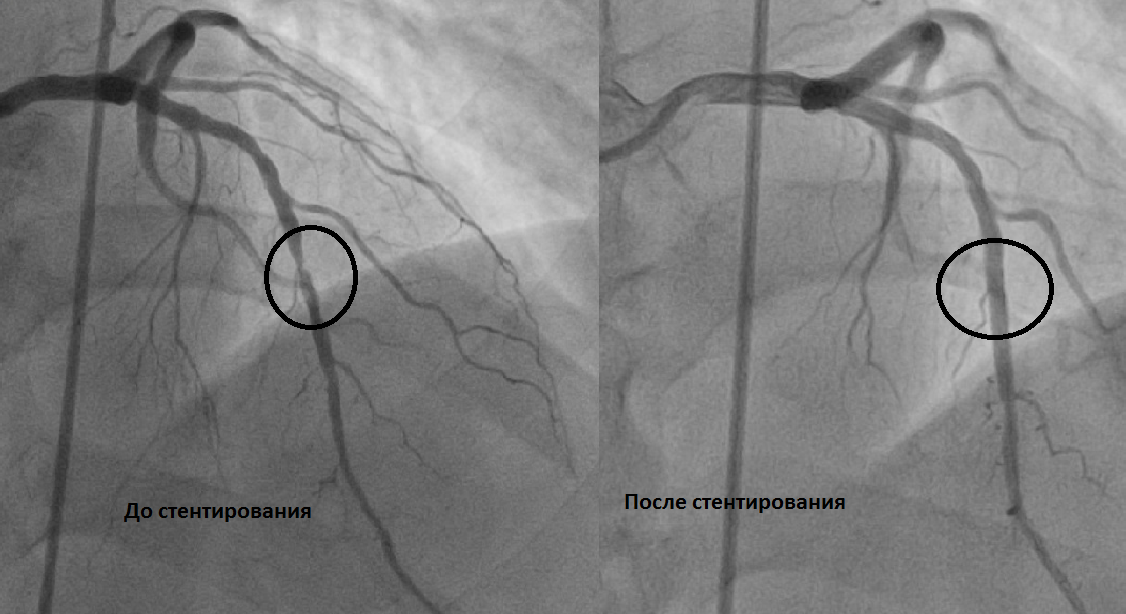

Если вы читали мою предыдущую статью, то знаете что я перенесла два стентирования коронарных артерий.

Мне предстояла вторая оперция через 3 месяца. Как она прошла я подробности не буду писать, скажу только легче чем первая. И реабилитация прошла легко. Через неделю я уже вышла на работу.